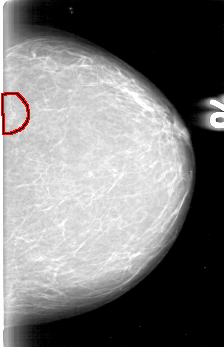

D_4003_1.RIGHT_MLO

LEFT_MLO LINES 5386 PIXELS_PER_LINE 3811 BITS_PER_PIXEL 12 RESOLUTION 43.5 OVERLAY

FILE: D_4003_1.LEFT_MLO.OVERLAY

TOTAL_ABNORMALITIES 1

ABNORMALITY 1

LESION_TYPE MASS SHAPE IRREGULAR MARGINS OBSCURED

ASSESSMENT 0

SUBTLETY 4

PATHOLOGY BENIGN

TOTAL_OUTLINES 1

BOUNDARY